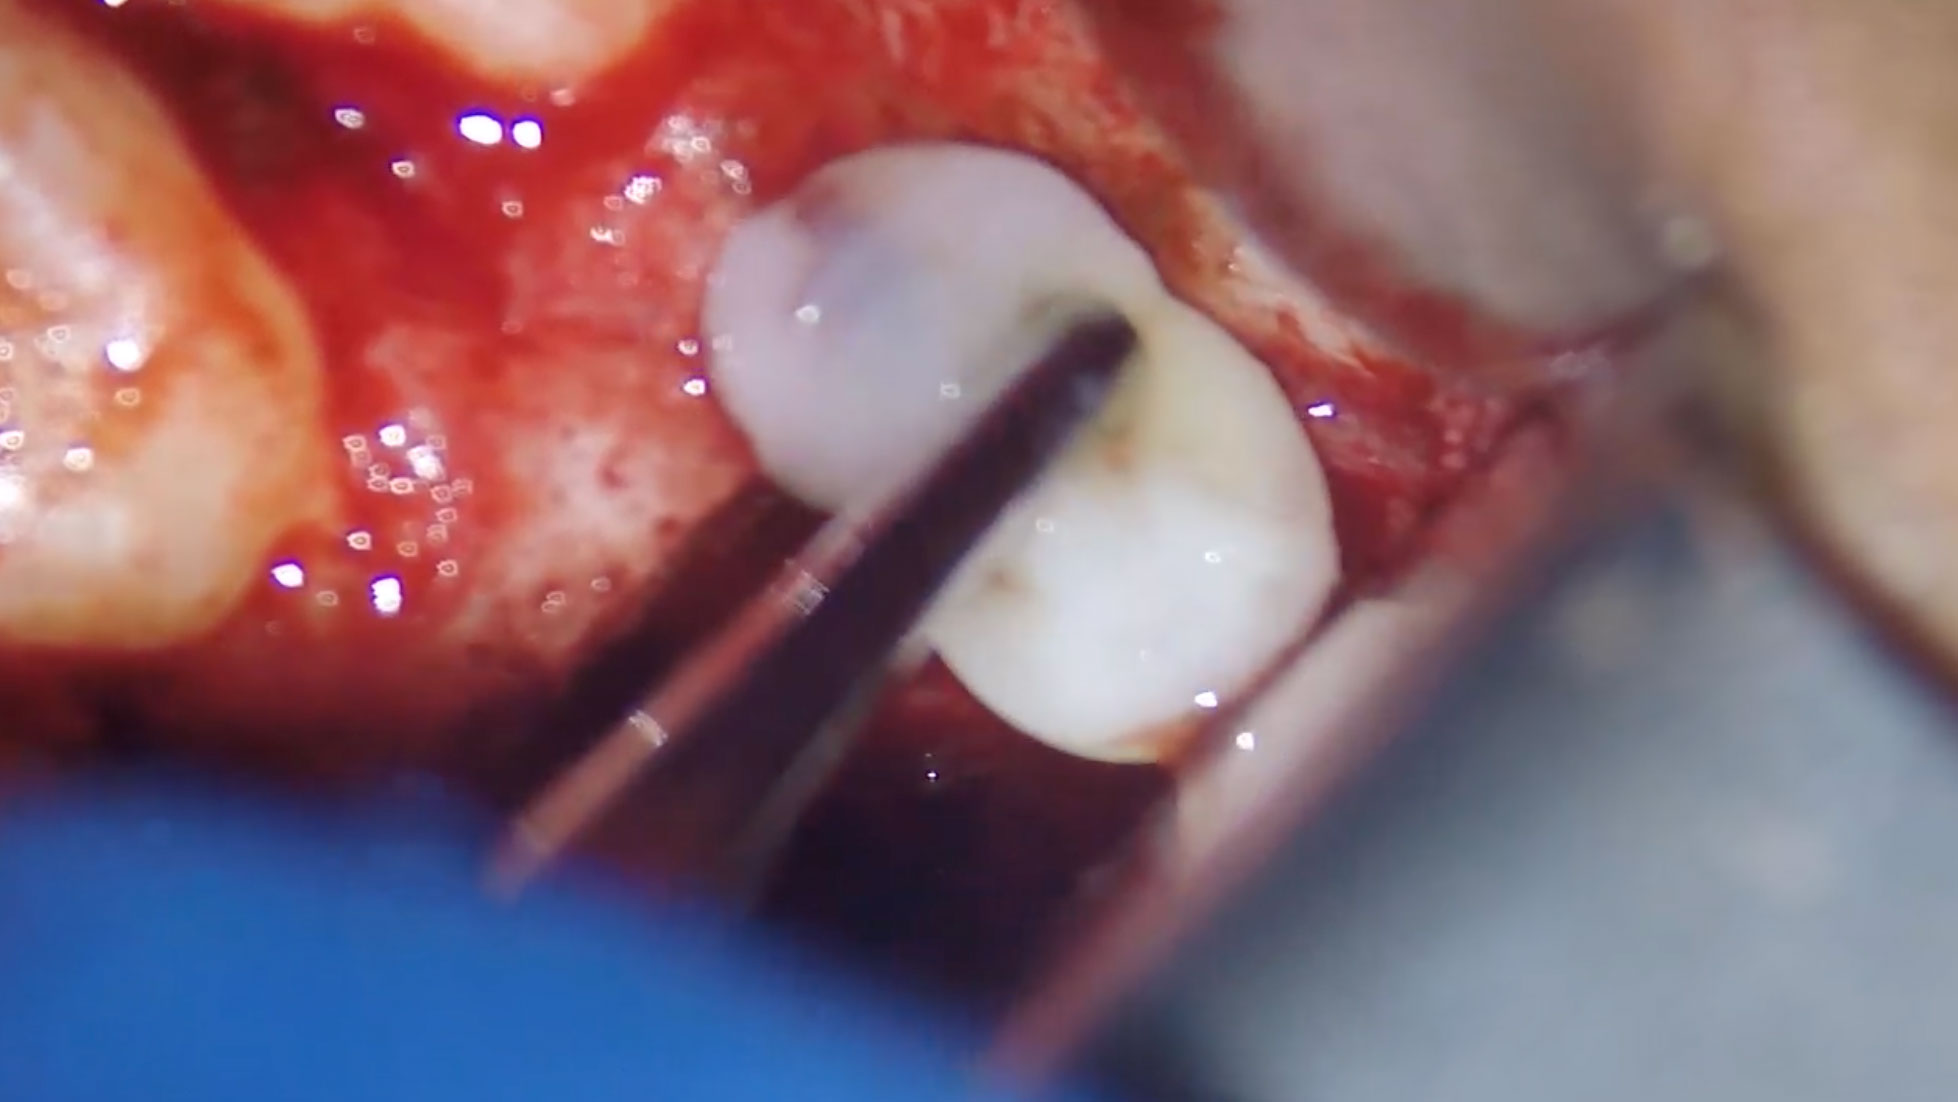

Deep Shape in Endodontics: Significance, Rationale and Benefit

The goal of endodontic treatment is to prevent or cure, when present, Lesions of Endodontic Origin, at times referred to as apical periodontitis. The role of bacteria in the pathogenesis of endodontic disease is well established, and therefore, it is critical to eradicate these pathogens by employing the highest level of presently developed standards. This … Read more